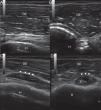

La ecografía en manos del internista permite responder preguntas clínicas concretas de forma rápida en el lugar de atención al paciente. Esta técnica «potencia» los sentidos del clínico y mejora su capacidad para resolver los problemas del enfermo. La ecografía clínica ha mostrado una buena precisión en el diagnóstico de diversas patologías cardíacas, abdominales y vasculares. También es útil para la evaluación de la patología tiroidea, osteoarticular y de partes blandas. Además, el uso de la ecografía para guiar procedimientos invasivos (accesos venosos, toracocentesis, paracentesis) reduce el riesgo de complicaciones. Presentamos 5casos para ilustrar la utilidad de esta técnica en la práctica clínica habitual del médico internista: a)miocardiopatía periparto; b)ateromatosis carotídea subclínica; c)aneurisma de aorta abdominal asintomático; d)tendinitis de los tendones largo del bíceps braquial y supraespinoso, y e)hematoma espontáneo en sóleo.

Ultrasonography in the hands of the internist can answer important clinical questions quickly at the point of patient care. This technique “enhance” the senses of the physicians and improves their ability to solve the problems of the patient. Point of care ultrasonography performed by clinicians has shown good accuracy in the diagnosis of diverse cardiac, abdominal and vascular pathologic conditions. It may also be useful for evaluation of thyroid, osteoarticular and soft tissue diseases. Furthermore, the use of ultrasound to guide invasive procedures (placement of venous catheters, thoracentesis, paracentesis) reduces the risk of complications. We present 5cases to illustrate the usefulness of this technique in clinical practice: (i)peripartum cardiomyopathy; (ii)subclinical carotid artery atherosclerosis; (iii)asymptomatic abdominal aortic aneurysm; (iv)tendinitis of long head of biceps brachii and supraspinatus, and (v)spontaneous soleus muscle haematoma.